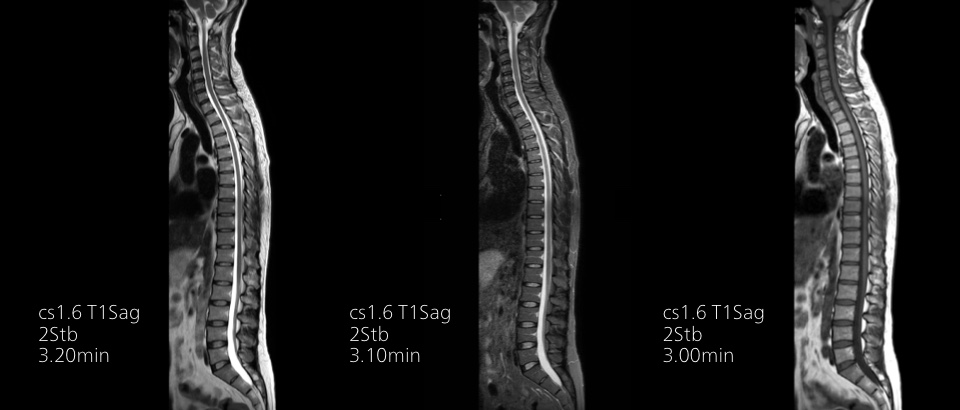

Compressed SENSEは、実質的に同等の画質を保ちつつ、撮像時間を最大50%²高速化します。

時間を味方につける - Compressed SENSEを使用すると、実質的に同等の画質を保ちつつ、撮像時間を最大50%²短縮できます。空間分解能が60%向上した高品質のMR画像を得ることで確実な診断が可能になります。

Philips Breezeコイルは、正確な解剖学的構造や非常に小さな関節を撮影するための優れた汎用性を備えています。最大55 cmの広い撮像視野と優れたSNRにより、高い画質が得られます。